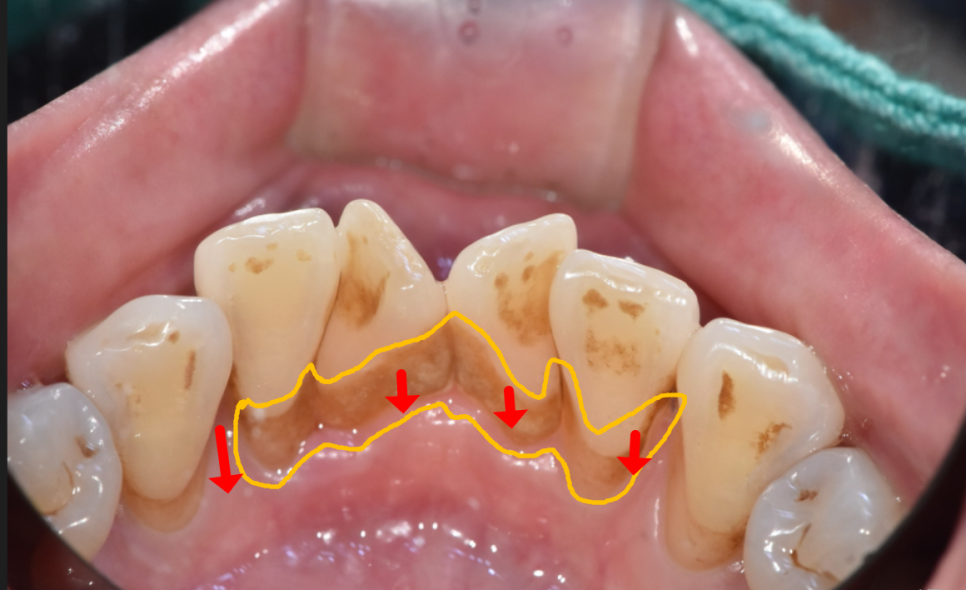

치석으로 인해 내려간 잇몸

치아와 잇몸 사이 틈새에 치석이 쌓이면서

잇몸에 염증이 시작되고,

아래 치조골(잇몸뼈)을 녹이면서

잇몸도 따라 내려가게 됩니다.

옆으로 양치하는 습관으로 생긴 치경부마모증